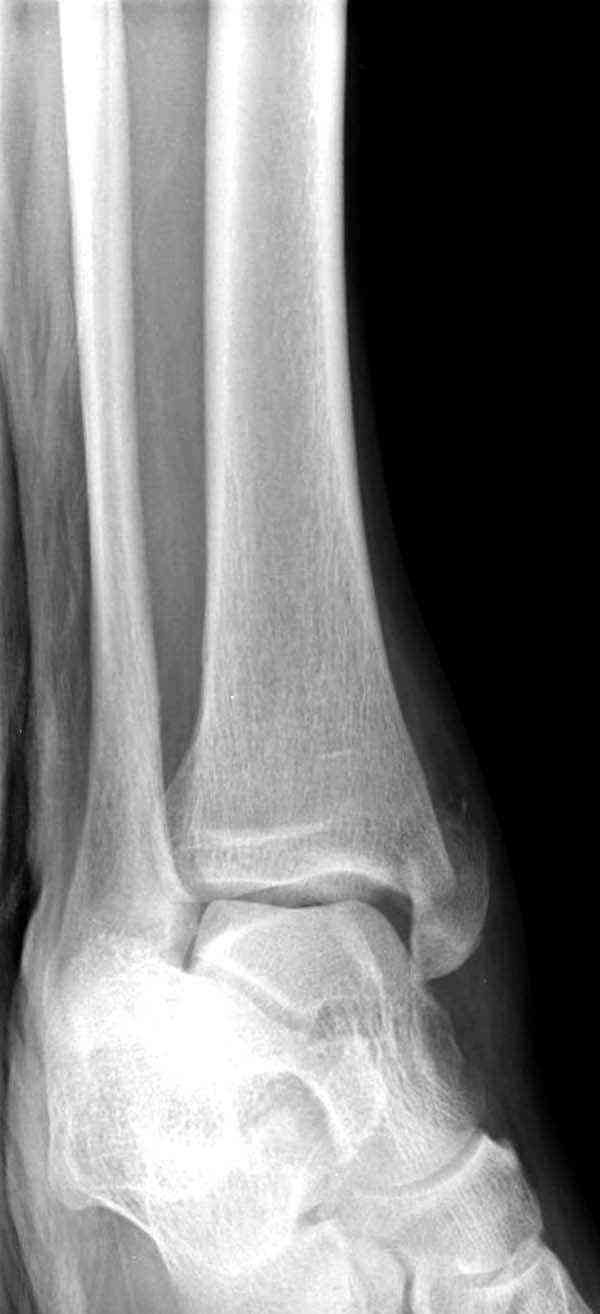

Случай прошлого года:пациентка-молодая ,крупная женщина ,30лет.Травма в начале апреля 2009г-пронационный перелом лодыжек с подвывихом стопы.Ко мне обратилась через 35 дней,прооперирована 22.05.2009г.Внутренняя лодыжка фиксирована по Веберу,наружная реконструктивной пластиной с наложением болта-стяжки.Иммобилизация "сапожок" в течении месяца,затем пригипсовано "стремя".Гипс снят 10.07.2009г

Достаточно быстрое восстановление функции.В октябре 2009г-почувствовала боль,в области рубца над гайкой открылся свищ.На Р-граммах-консолидация переломов и смещение гайки по стяжке.10.11.2009г-конструкции удалены,санация,заживление ран.В настоящее время пациентку ничего не беспокоит.На операции-раскручивание гайки-болталась на конце стяжки.Вопросы:какой механизм раскручивания и что я неправильно сделал?Свои версии:1)в области синдесмоза успела образоваться рубцовая ткань,которая при движении в суставе"пружинила",поскольку голеностопный сустав является спиральным, то и биомеханика подобна кривошипному механизму.2)Реконструктивная пластина не "реконструировалась" по форме лодыжки.Наложил,как есть.То есть подпружинивала сама пластина.Ну,это мои догадки.Что нужно,чтобы избегать впредь таких,пусть и не "страшных"осложнений:Рассверливать через лодыжку область синдесмоза?Ставить шайбу-гровер?Тщательно моделировать пластину?Прилагаю сравнительные снимки-сразу после операции и перед удалением конструкции.